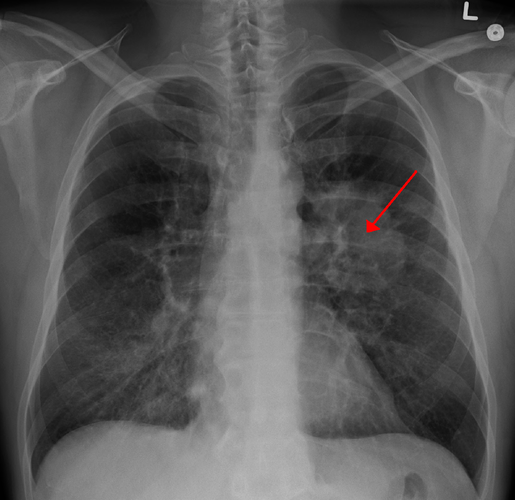

Khi nhắc đến bệnh ung thư phổi, đầu tiên nhiều người sẽ nghĩ ngay đến các triệu chứng như ho, khó thở, ho ra máu,… Tuy nhiên, căn bệnh này có thể di căn ở một số vị trí khác trong cơ thể. (Ảnh: wcrf.org)

Chẳng hạn, gần đây, một bệnh nhân nhập viện điều trị ngoại trú do lên cơn đau đầu và tưởng là tai biến mạch máu não. (Ảnh: acc.vn)

Qua thăm khám, bác sĩ phát hiện một khối u di căn nội sọ, và khi kiểm tra kỹ hơn thì phát hiện khối u nguyên phát nằm ở phổi. Ảnh: Boldsky.

Do ung thư phổi rất dễ di căn ở đầu nên khi có một số tín hiệu bất thường ở đầu, bạn cũng nên cảnh giác với vấn đề sức khỏe của phổi. (Ảnh: MedicineNet)